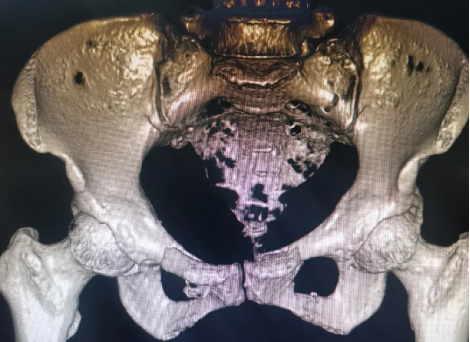

患者黄某,因车祸外伤导致全身多处疼痛入院,入院即因失血性休克于ICU监护,完善检查显示双侧耻骨粉碎性骨折、右侧髂骨多处骨折、右骶髂关节脱位,提示骨盆前-后环均不稳定。

对于此种前后环均严重失稳的复杂骨盆骨折的治疗,保守治疗不仅需长期卧床,易导致褥疮、肺部感染、泌尿系感染及深静脉血栓风险,同时势必影响后期功能恢复,严重降低患者未来生活质量。传统开放术式手术切口大、手术时间长,手术难度极大,同时存在盆腔内血管神经及膀胱的医源性损伤风险,以往,遇到此种严重病情只能依赖上级医院专家来院手术指导,但基于近期成功开展的骨盆微创治疗的经验支持,外一科董明主任反复研究患者病情及影像,充分考虑手术创伤与风险后,决定开展骨盆骨折有限切开复位内固定术。